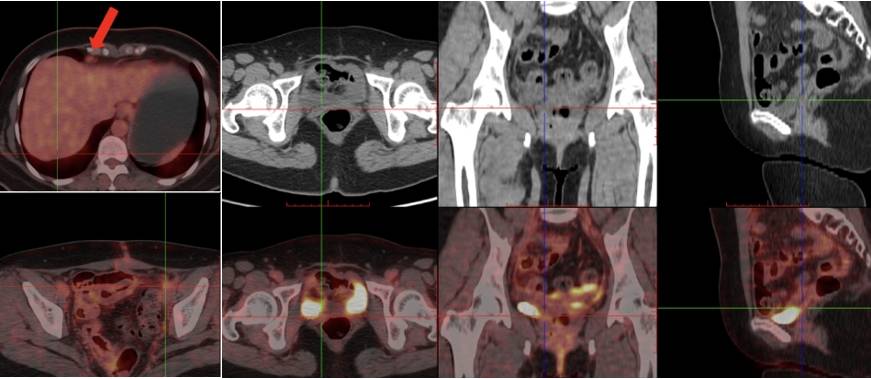

腹盆腔增强CT:1. 肝VI段包膜下稍低密度灶,左侧髂血管旁结节,转移可能大。2. 卵巢癌术后,盆腔腹膜局部稍增厚。3. 双侧肾上腺结节。4. 肝内散在囊肿。5. 腹膜后散在稍大淋巴结。

PET-CT: 1、①卵巢癌术后,子宫及双附件缺如,阴道残端未见明确肿瘤征象。②肝S7段包膜下稍低密度灶,FDG代谢增高,考虑转移。③左侧髂外血管旁肿大淋巴结,FDG代谢增高,转移可能大。④左侧盆底(乙状结肠左旁)结节伴高代谢,倾向转移灶。2、双侧筛窦及左侧上颌窦炎。双侧扁桃体区对称性FDG代谢增高,考虑炎性增生。3、右肺上叶前段结节,FDG代谢未见明显异常增高,倾向炎性病变。双肺多发小增殖灶。4、肝内多发囊肿。 5、双侧肾上腺结节,考虑腺瘤。6、腹膜后、双侧腹股沟多发增大淋巴结,炎性增生可能性大。

PET-CT(2022年11月1日):对比2022年1月6日PET-CT,1、①卵巢癌术后改变,阴道残端未见明确肿瘤征象,较前相仿;②盆底腹膜、左下腹膜局部明显增厚伴FDG代谢增高,FDG代谢增高,较前新发,考虑转移;③肝脏术后改变考虑,局部少量积液;④右侧心膈角肿大淋巴结伴FDG代谢增高,较前新发,考虑转移;⑤肠系膜间隙、结肠旁及腹膜后多发淋巴结,部分FDG代谢略增高,较前相仿。2、左侧筛窦及左侧上颌窦炎。双侧扁桃体炎。3、右肺上叶前段结节,FDG代谢未见明显异常增高,较前相仿,倾向炎性病变。4、肝内多发囊肿,较前相仿。肝右叶钙化灶。5、右侧肾上腺显示欠清,左侧肾上腺略增生,较前大致相仿。6、双侧腹股沟多发炎性增生淋巴结,较前相仿。